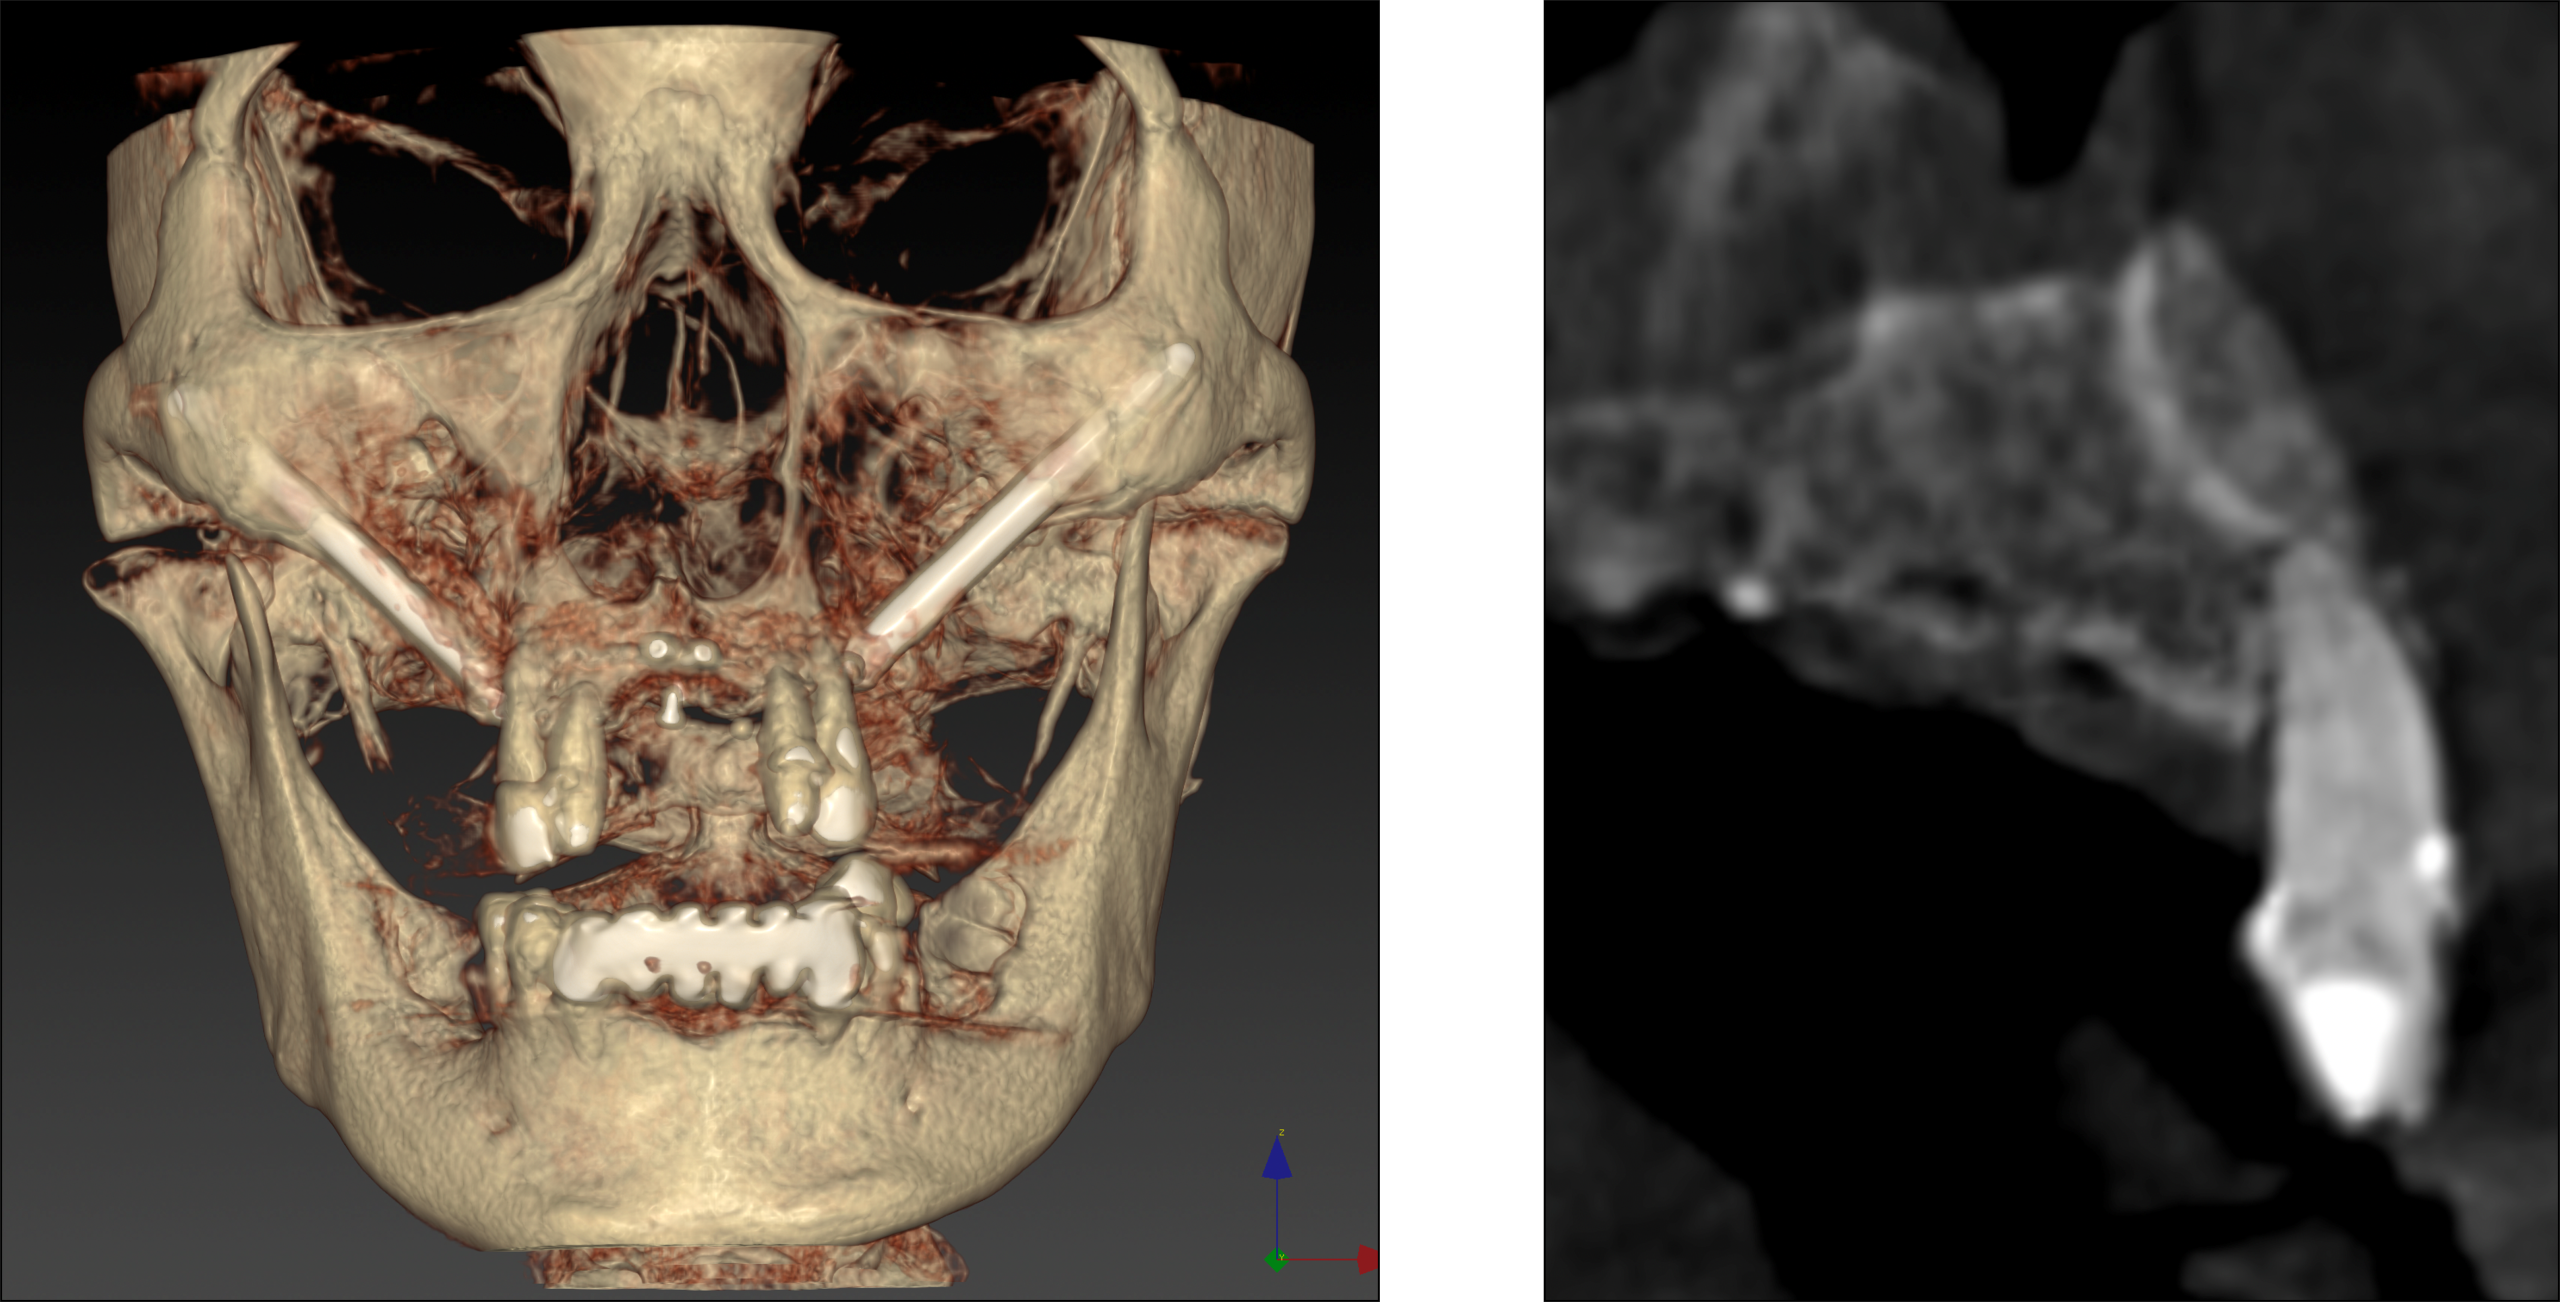

3.15,25 staged zygoma implant

15,25 staged zygoma implant surgery + sinus augmentation & UA contour GBR

▍第二次手術 thin sinus wall

4 個月後, 前牙區basal bone GBR有癒合,進行 #12,22 植牙,完成上顎All-on-5手術

第二次當日手術後進行Navigated Photogrammetry